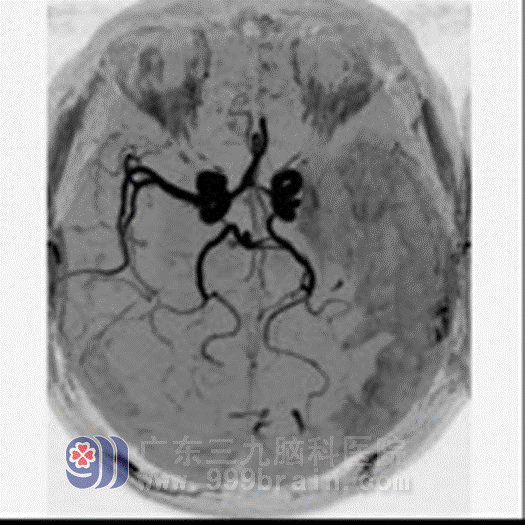

He reviewed a month later:

The colloid substance around infarction section increased. MRA showed his left brain still had artery emphraxis.